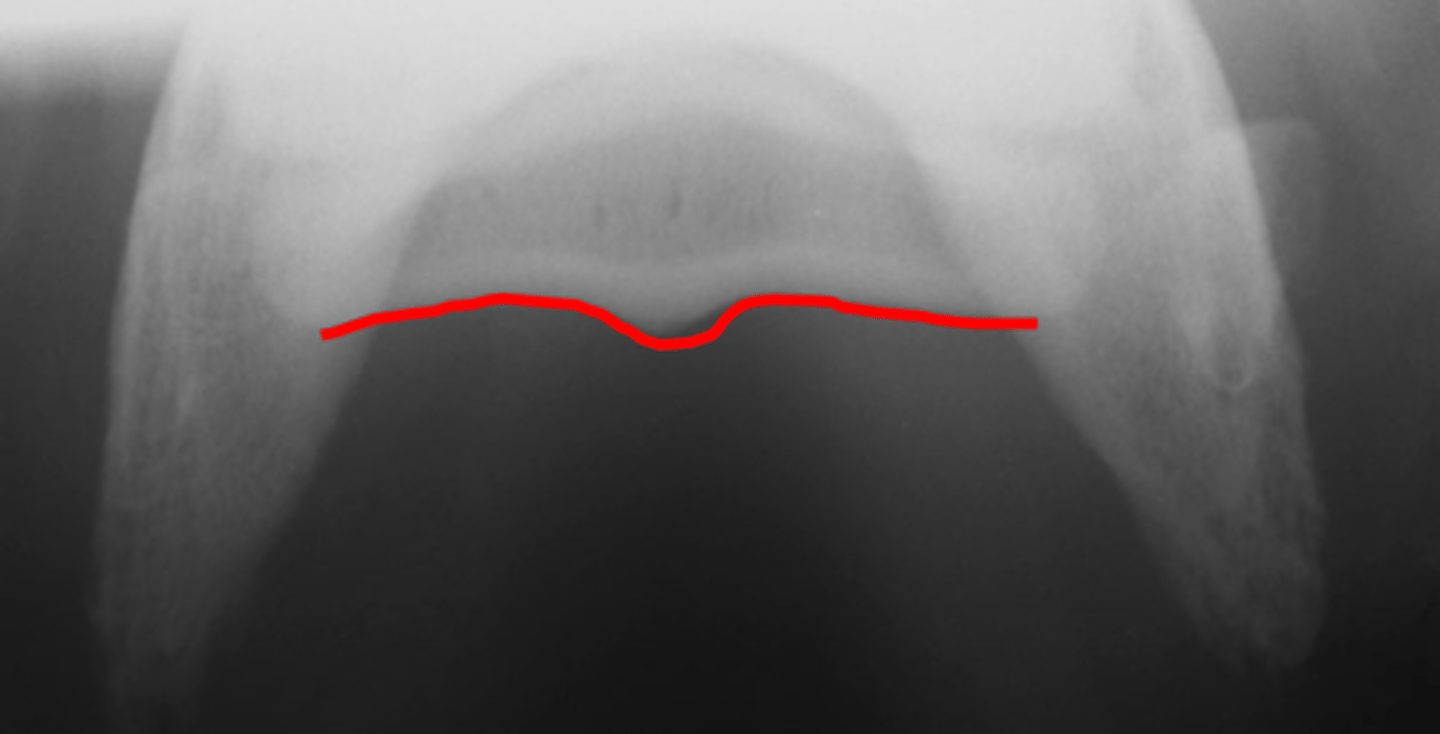

Flexor skyline

What view is this?

1. Flexor surface

2. Corticomedullary distinction

3. Number of synovial invaginations

What is the flexor skyline used to evaluate?